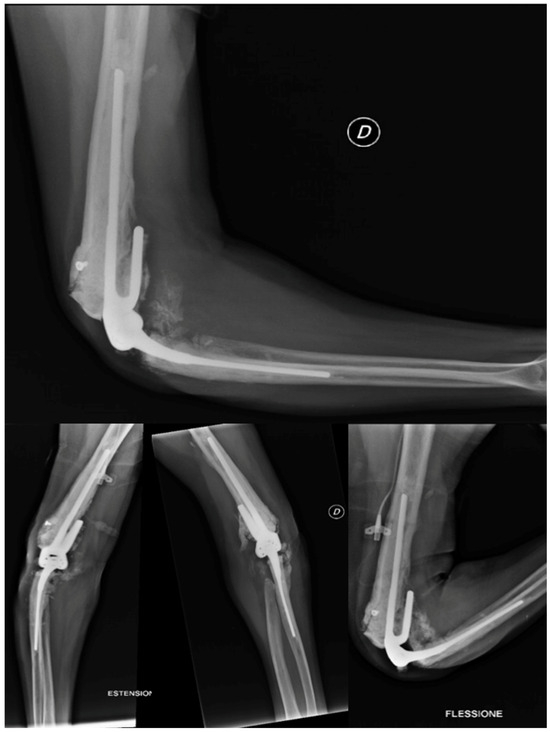

2.4.6. Revision Total Elbow Arthroplasty

- Evidence from the Scientific Literature

3. Discussion